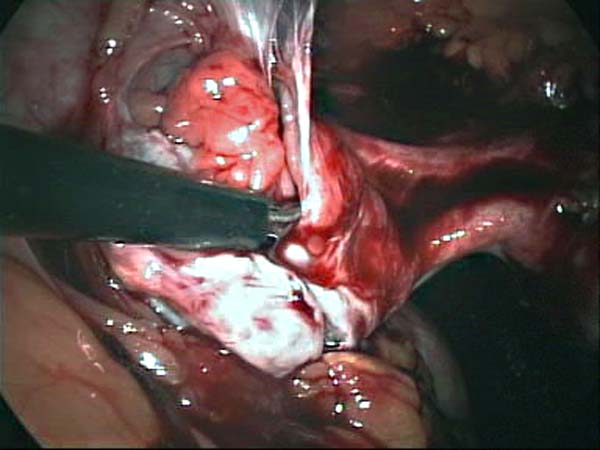

- Laparoscopy Photos 1

- Laparoscopy Photos 2

- Laparoscopy Photos 3

- Laparoscopy Photos 4

Laparoscopy Photos Polycystic Ovaries adhesiolysis IUCD Through Uterine Wall | Dr N Layyous